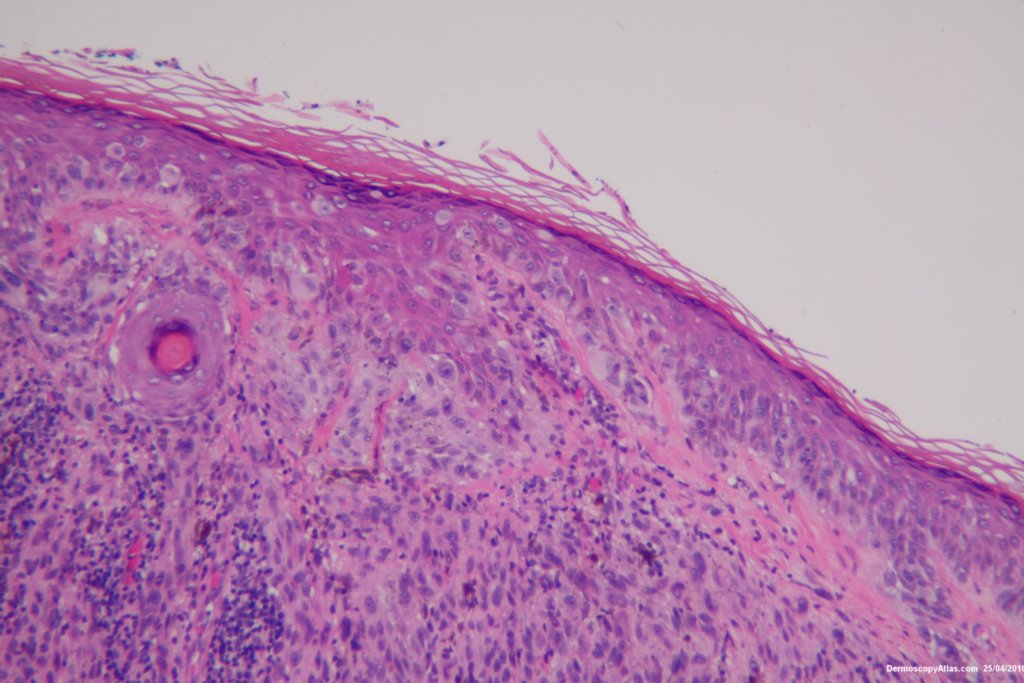

Diagnosis: Melanoma invasive

This 57 years old male presented with a lesion on his thigh that he said had only been present for 6 weeks. It looked and felt keratotic and had a bluish discolouration associated with it. It was thought to be an irritated Seborrhoeic keratosis perhaps with some bleeding into it to account for the blue colour.

The shave biopsy was reported as a level 4 Invasive melanoma 1.7 mm thick with 3 mitoses per high powered field. There were no groin glands enlarged clinically.